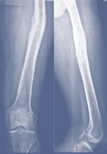

Case-III

62 years, female;

Broken IMN of fracture tibia and fibula (Implant failure) (Figure 11-13).

Figure 11 X-ray broken IM nail after fall.

Figure 12 Post-operative x-ray after Ilizarov operation.

Figure 13 X-ray after union.